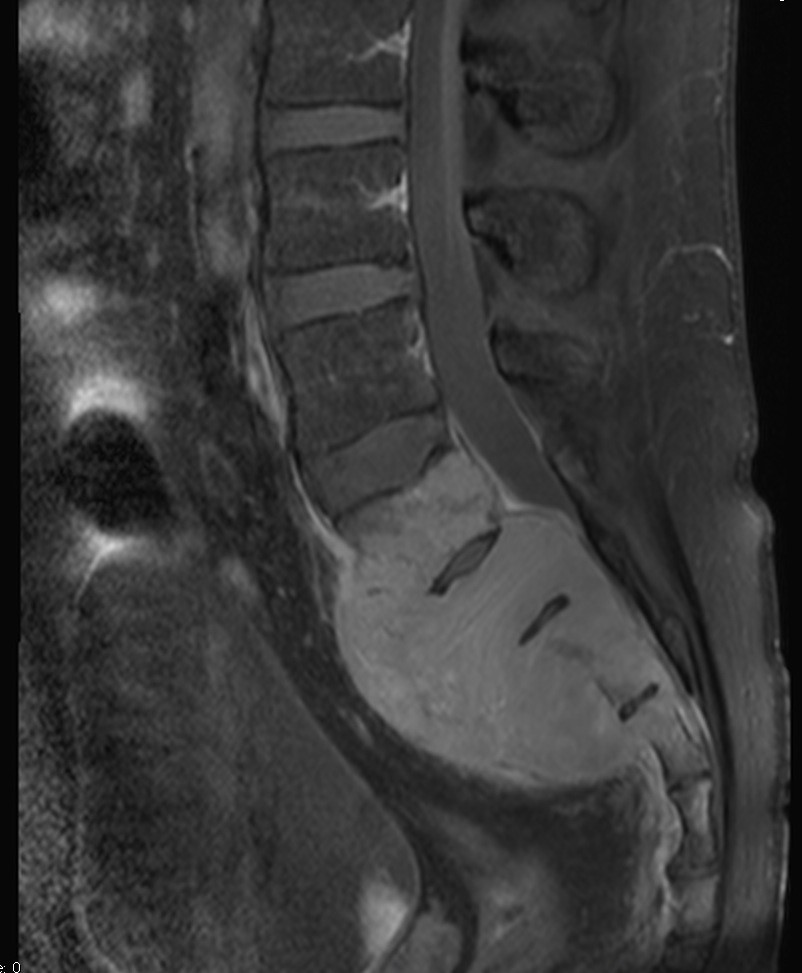

Primary lymphoma of the sacral bone is a rare myeloproliferative disease, occurring mostly after 4th decade of life and mainly in male patients. We reported a case of sacral bone lymphoma in a 24-year-old man with low back pain and radiculopathy. Imaging showed a sacral bone lesion which later proved to be non-Hodgkin’s lymphoma on histopathologic study. Lymphoma of the sacral bone is chemoresponsive and carries a good prognosis. Sacral bone lymphoma should be considered as a differential diagnosis in patients with low back pain who is not responding to analgesic treatment.